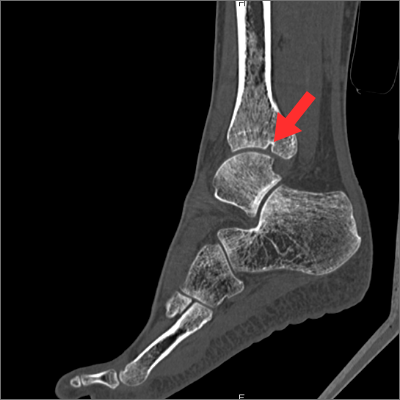

たとえば、12級の「右足首の動かせる範囲が4分の3以下」は、

- 右足首の動かせる範囲が4分の3以下になったこと

- 1の後遺症の原因となる右足関節部の骨が欠けていることがCT画像で証明できること

の2つが揃えば認定されます。